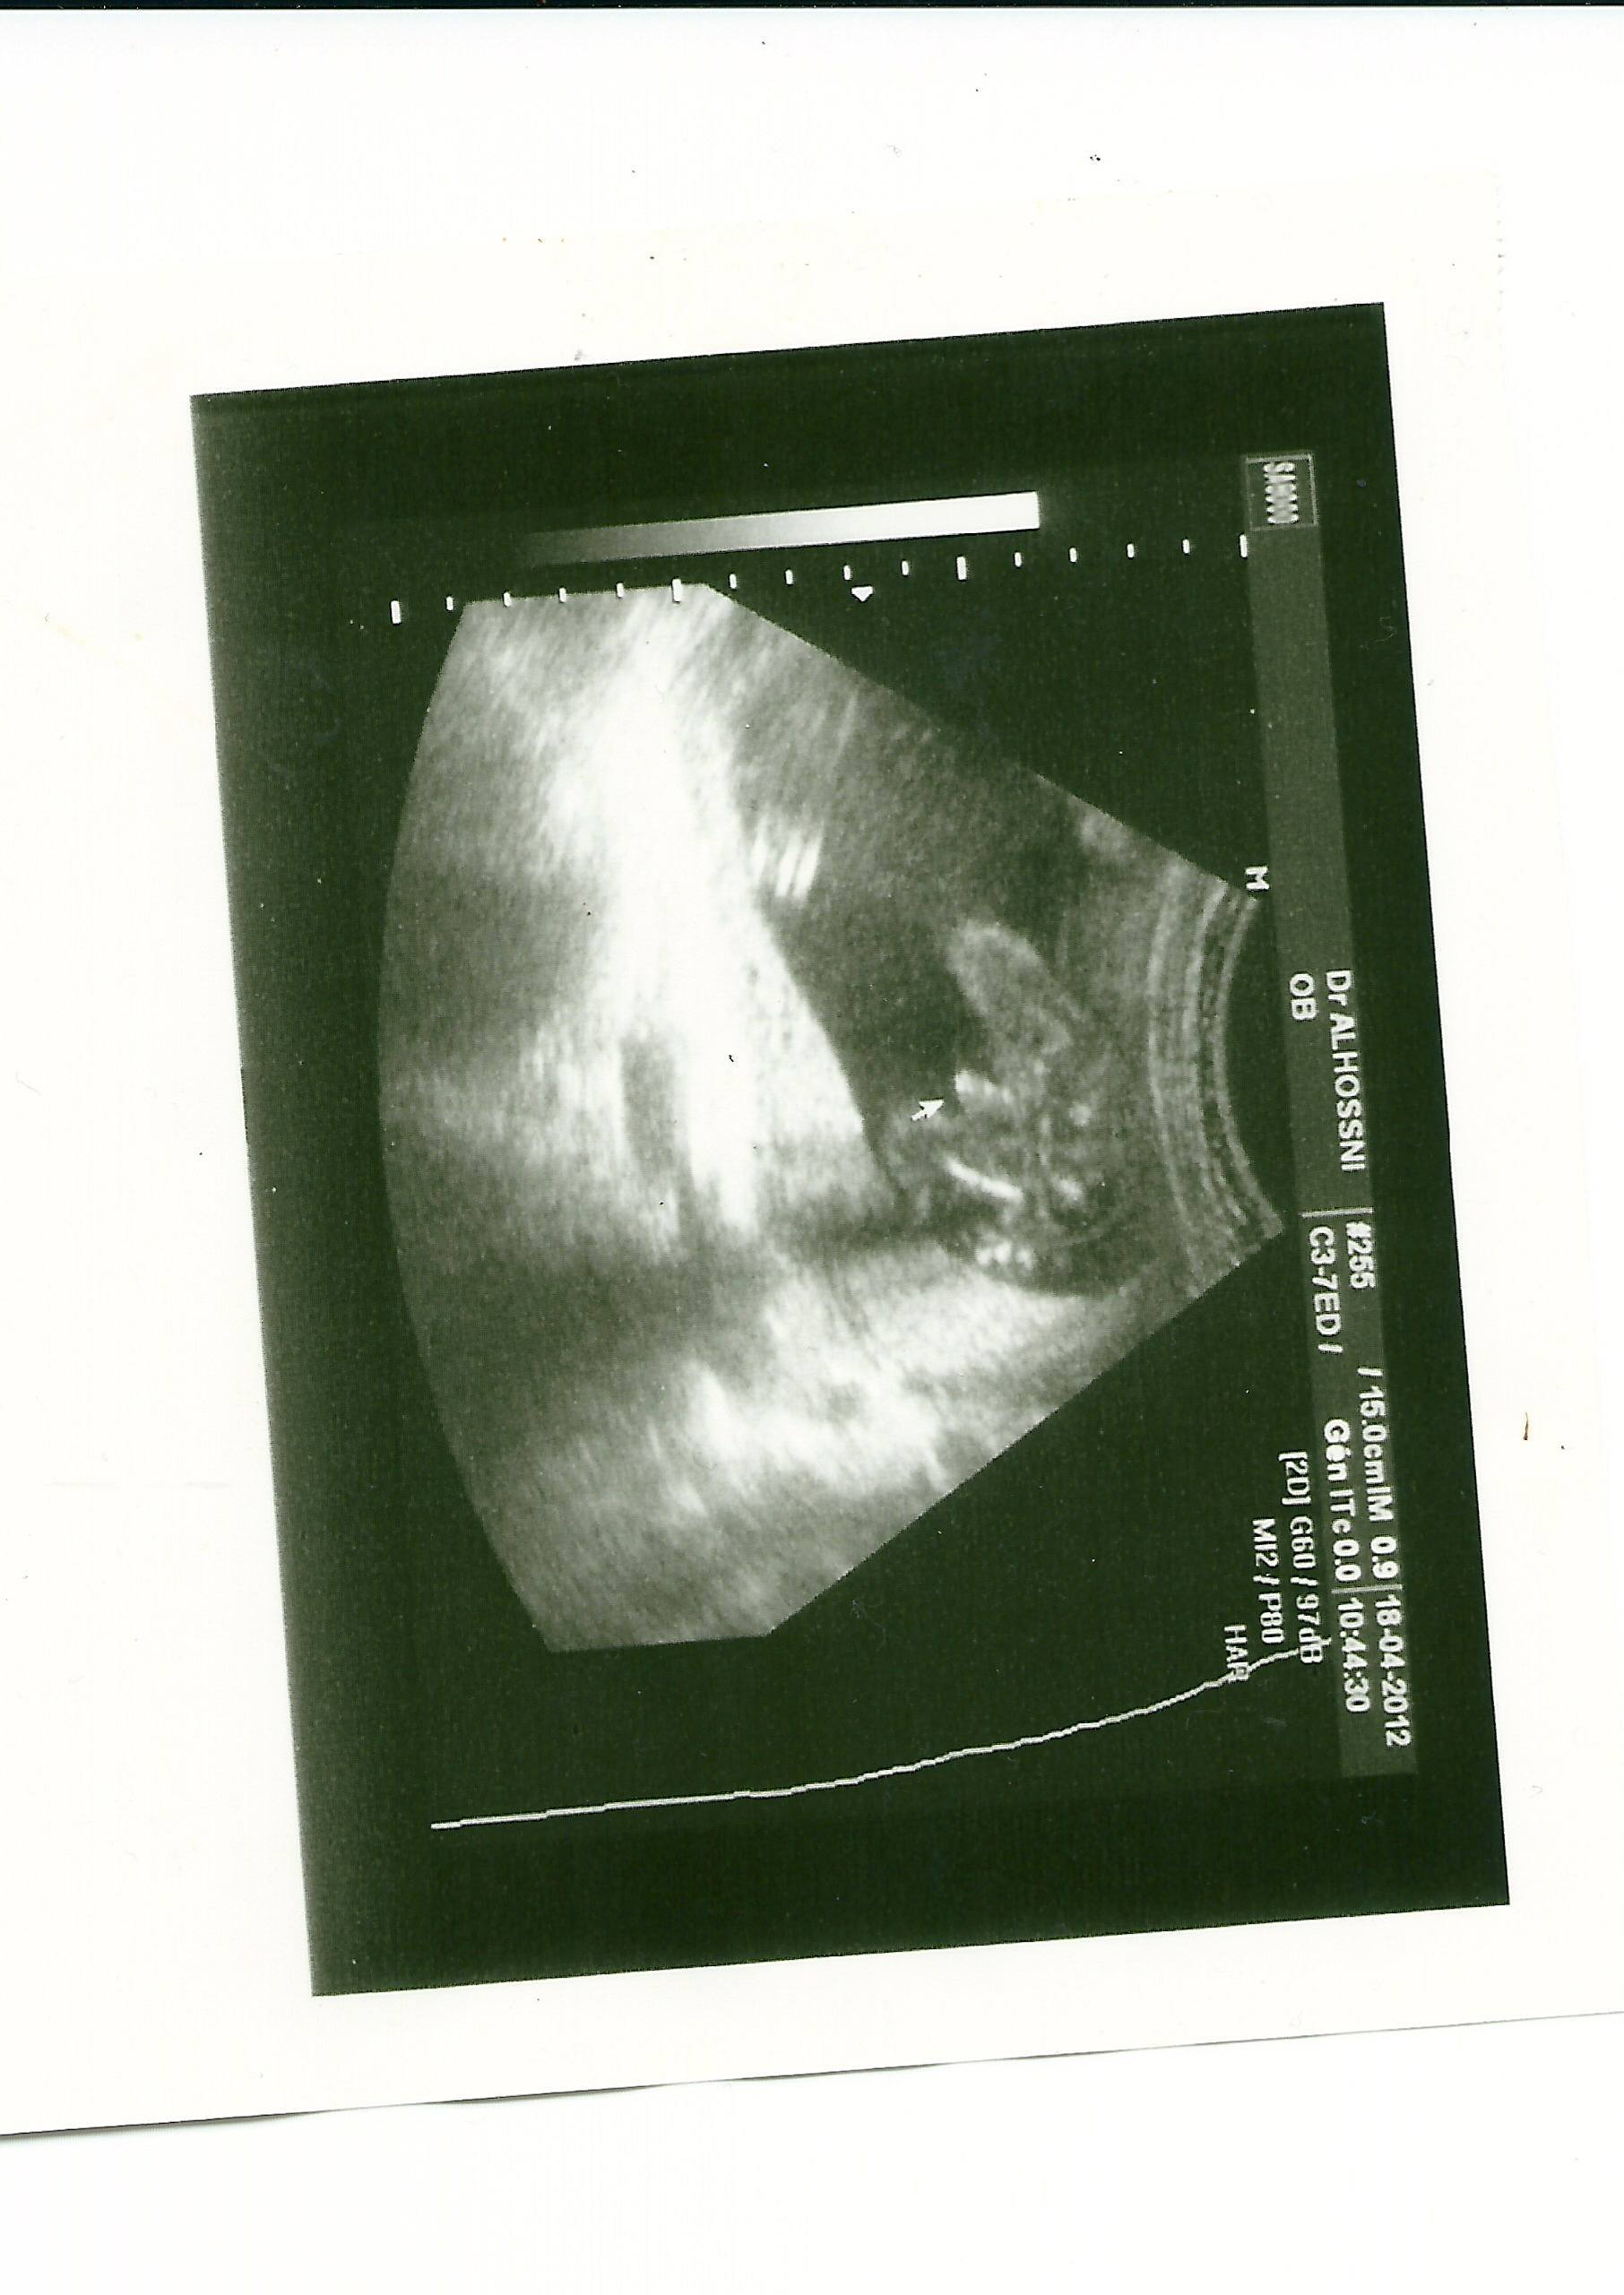

coucou les filles me revoila avec toujours mon probleme de sexe de bebe lol alors pour recap a 3 mois garcon a confirmer et a 3 mois et 3 semaines filles puis garcon a voir et a 4 mois voila lecho soit disant garcon mais moi jy croit pas trop car si on regarde bien ce soit disant sexe fait presque la taille du femur de bebe mdr en gros tout le monde autour de moi le trouve juste enormes !!!!!vous en pensez quoi les filles serieux jen peux plus on est dans le doute total

oui la tienne on voit bien les testicules et le penis et en rapport avec les jambes ca va ca fait pas trop gros ( jai la meme pour mon fils ) mais la si on compare sur mon echo ce soit disant penis ( qui fait 3 boules en montant) il arrive presque au genou du bebe cest bizarre je trouve !

oui lol apparement ca serait ca ou y a la fleche mais si tu regarde bien ca fait 3 boules ( comme si cetait le cordon ) et moi cest la taille qui m impressionne cest aussi grand que son femur !!!!